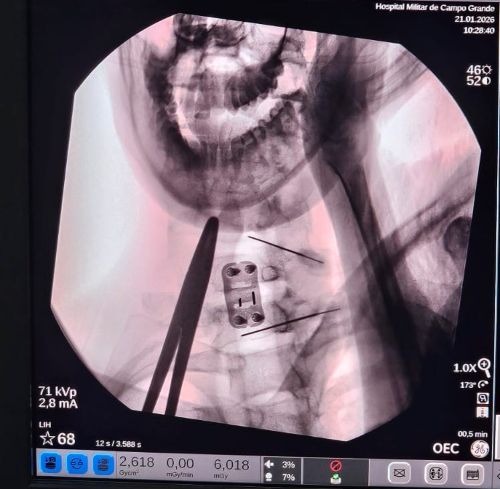

Comandada pelo neurocirurgião Bruno Cortez, do Hospital Souza Aguiar, do Rio de Janeiro, a equipe médica composta por profissionais do HMilACG utilizou um aparelho de radioscopia para visualizar, por meio de raio-x, a introdução da agulha na região lesionada, permitindo assim a infusão da proteína diretamente no tecido medular. O procedimento é considerado pouco invasivo, mas, delicado, exigindo precisão e perícia na execução.